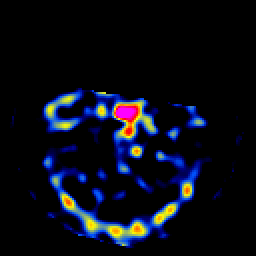

SPECT TL Study #8 -- Slice #15

[Home][Help][Clinical][Tour 1][Tour 2][Tour 3] Slice 15